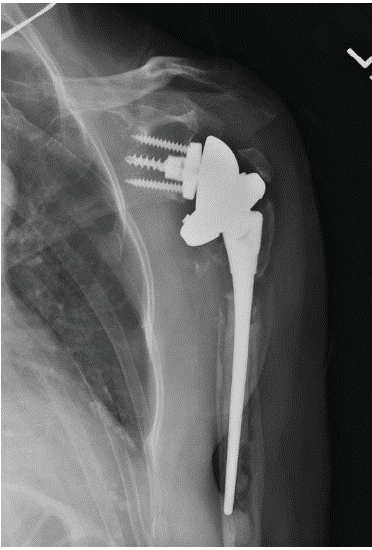

The patient was seen periodically after surgery with examinations and radiographs. At the 14-week post-operative appointment, she reported progressive shoulder pain without any trauma. The pain was exacerbated with any shoulder motion, and elevation was limited to 20°. Radiographs showed loosening of the humeral component (Fig. 3).

Figure 3: Anteroposterior radiograph showing infected primary reverse total shoulder arthroplasty. Note radiolucency around the implant.

The patient had no clinical signs of infection, such as redness, warmth, or drainage. Sedimentation rate and c-reactive protein were both normal. The joint was subsequently aspirated under sterile conditions, and cultures were positive for coagulase-negative Staphylococcus and Propionibacterium granulosum 4 days later.